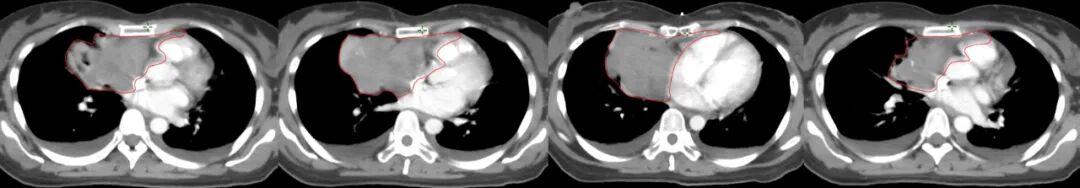

圖注:放射治療靶區(qū)及劑量分布圖。紅線是放射治療靶區(qū);綠色球體為放射治療高劑量分布,可見聚焦照射,周邊劑量快速跌落,周圍組織受到良好保護。